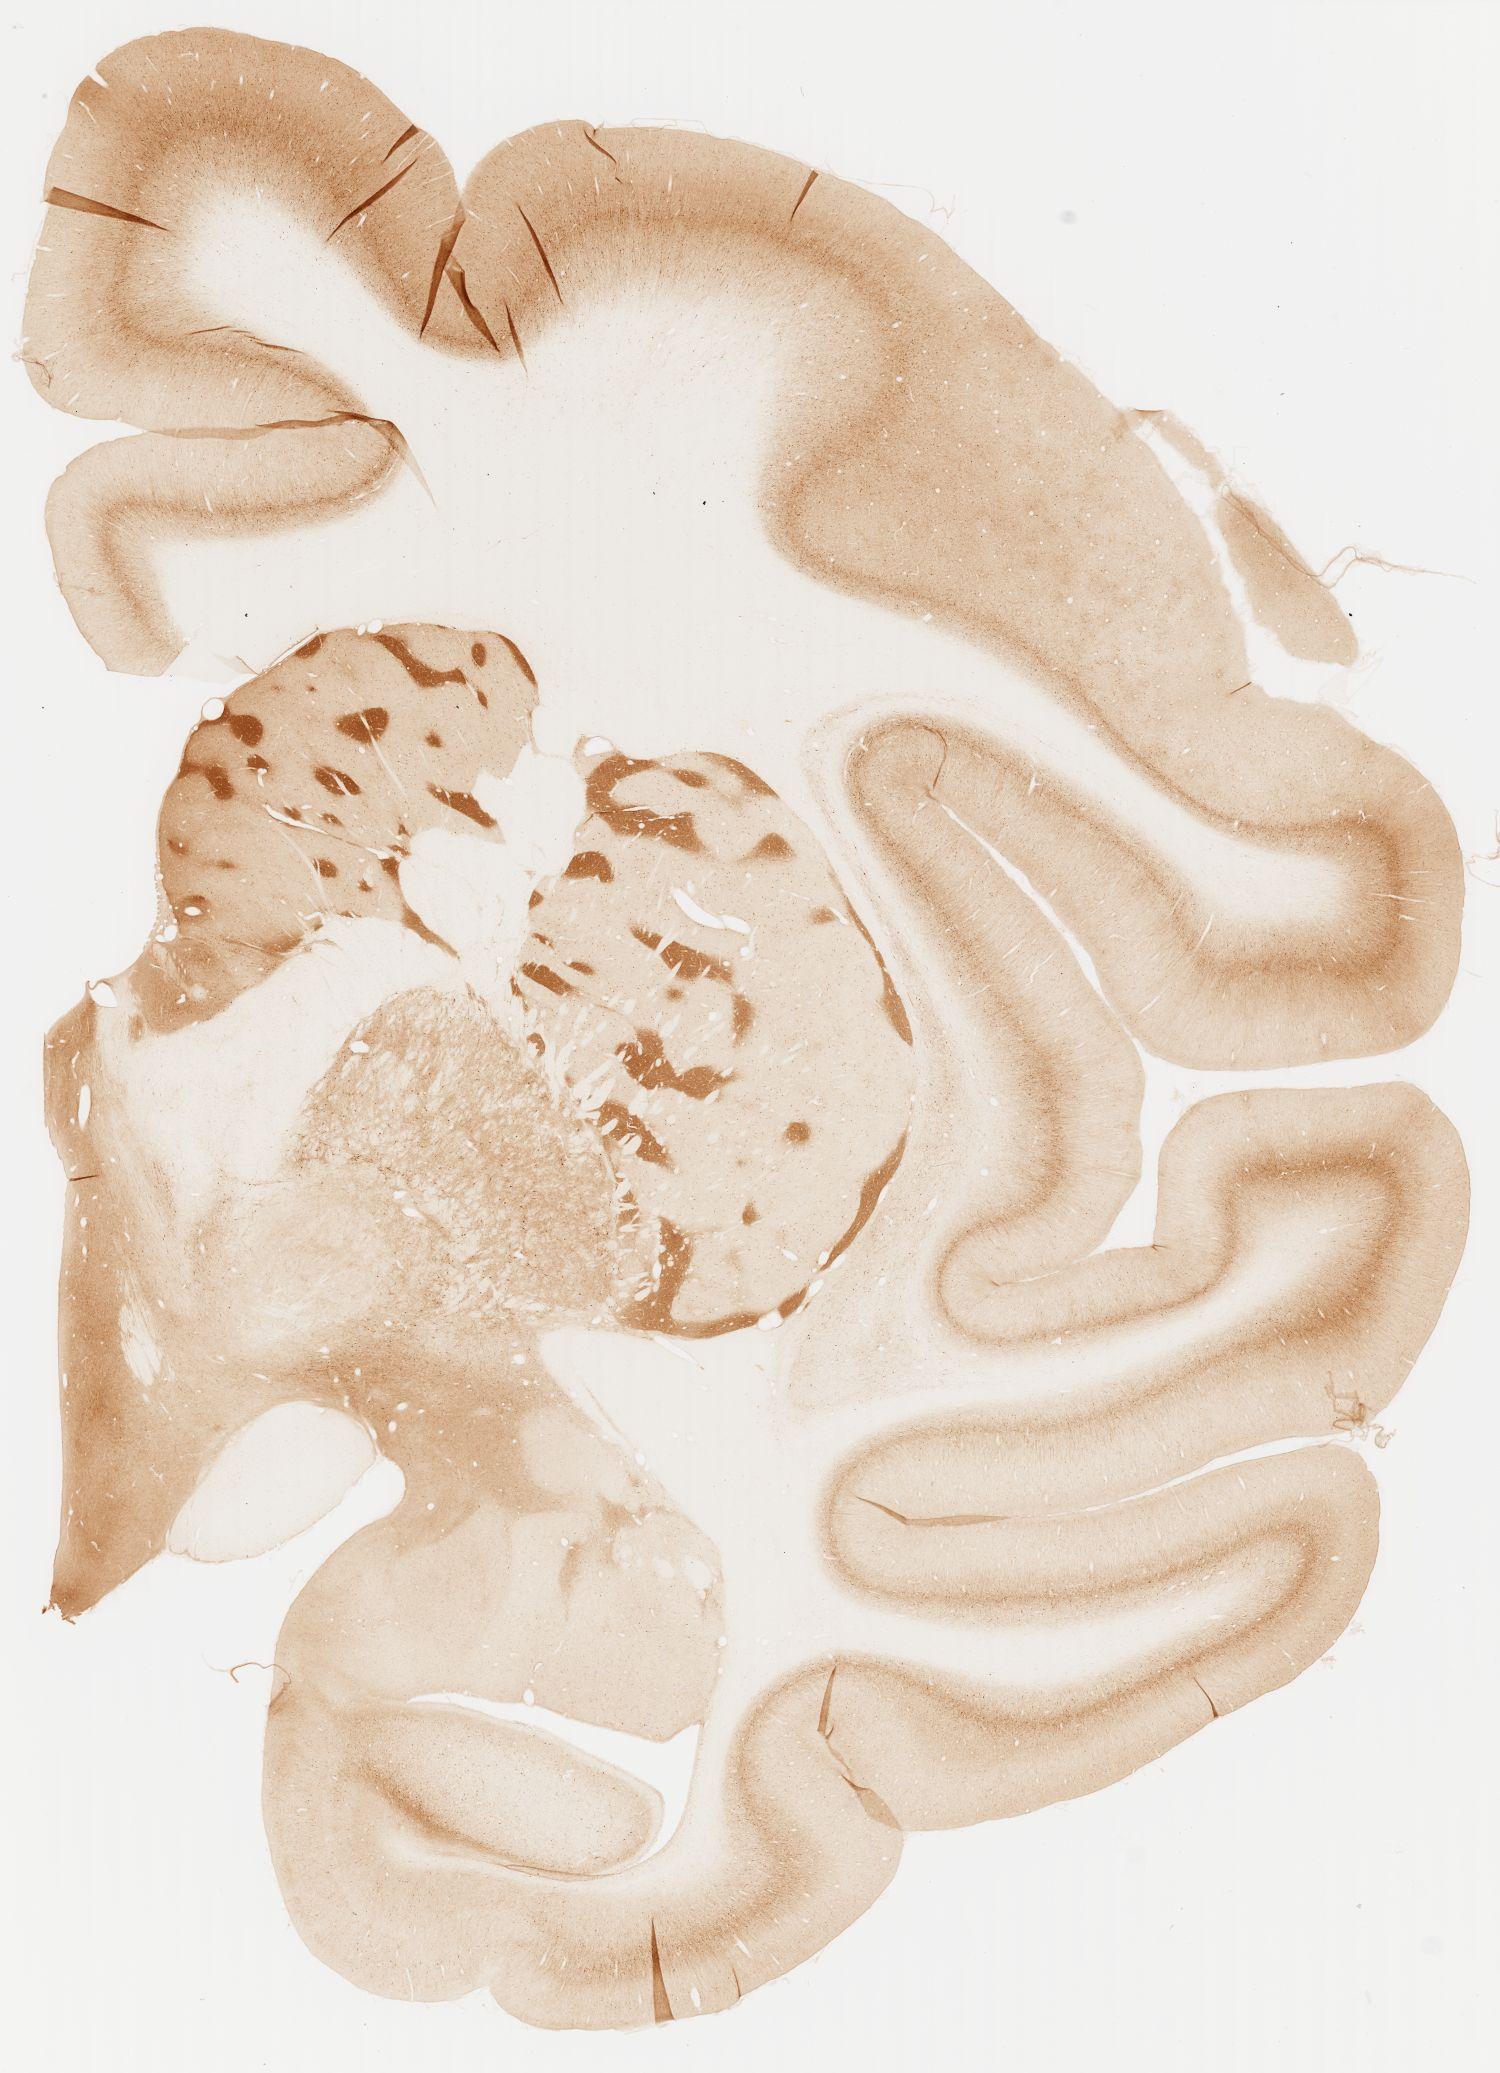

Datasets -> Macaca Fascicularis -> KChIP1, (Potassium Voltage-Gated Channel-Interacting Protein 1), coronal, immuno, Whole-Brain, adult

[ Metadata ]   ·   Source: Edward G. Jones